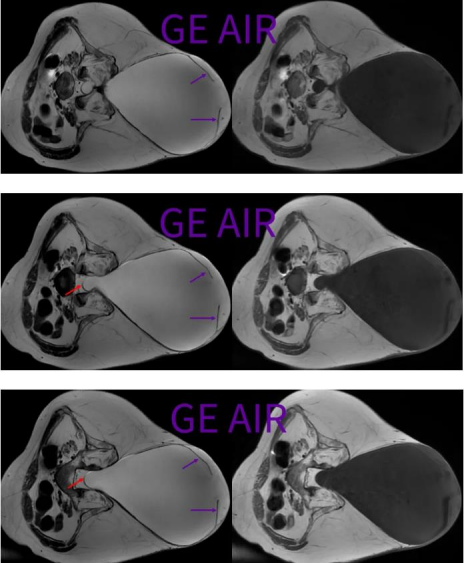

2.4 横断面CUBE T2和T1WI

横断面三维CUBE T2和T1,具有薄层(1mm)高分辨的优势,可以最小化脑脊液流动伪影和化学位移伪影,有助于椎管内和/或邻近椎管区域的病变解剖显示,建议偶遇非常规病例的时候,加扫这么一个序列。 所谓,我为人人,人人为我。